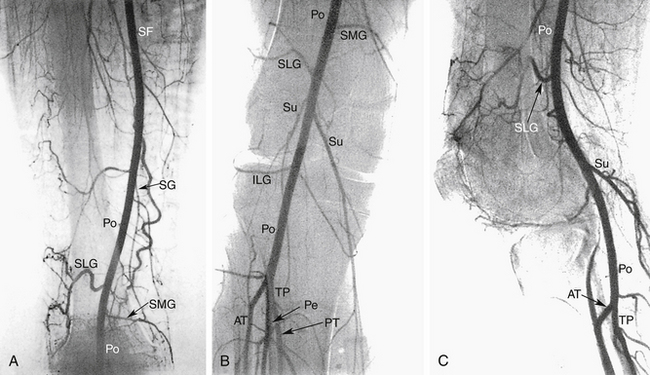

Артериальное дерево нижних конечностей начинается от бифуркации аорты, и эта часть сосудистой сети включена в эту главу. Подробную информацию об анатомии сосудов брюшной полости см. в главе 26 . Основные артерии нижних конечностей графически показаны на рисунке 13-8 . Рисунки с 13-9 по 13-13 представляют собой ангиографические изображения региональной артериальной анатомии нижней конечности.

РИСУНОК 13-12. Передняя большеберцовая артерия (ПП) идет переднелатерально от своего основания и проходит через межкостную перепонку. Затем он проходит вдоль передне-латеральной стороны голени к стопе. Большеберцово-перонеальный ствол (ТП) имеет переменную длину и обычно раздваивается на малоберцовую (Пе) и заднюю большеберцовую (ПТ) артерии. Малоберцовая артерия, также показанная на рис. 13-11 , Б , проходит вниз по ноге чуть выше лодыжки. Задняя большеберцовая артерия продолжается заднемедиальным путем до стопы. Po, подколенная артерия.

РИСУНОК 13-13. Косой вид правой стопы. Передняя большеберцовая артерия (АТ) переходит на тыльную поверхность стопы, где становится тыльной артерией стопы (DP). Задняя большеберцовая артерия (ПТ) проходит позади медиальной лодыжки и вскоре после этого раздваивается, образуя медиальную подошвенную (МП) и латеральную подошвенную (ЛП) артерии. Подошвенный свод стопы образуется путем слияния латеральной подошвенной артерии с подошвенной плюсневой ветвью (не показана) тыльной артерии стопы. Подошвенная дуга дает начало плюсневой и пальцевой ветвям.